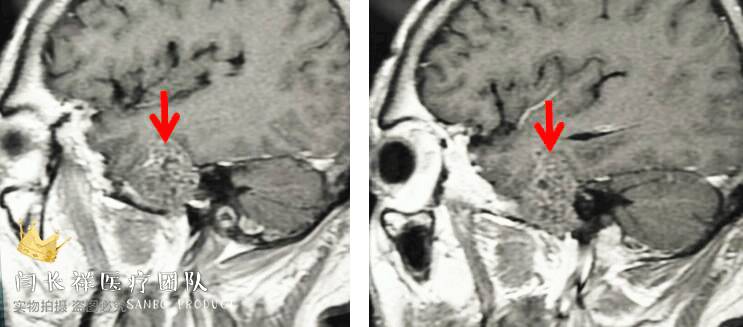

中颅窝-颞下窝占位

术前MRI轴位T1增强示病灶显著不均匀强化。

术前MRI矢状位T1增强。